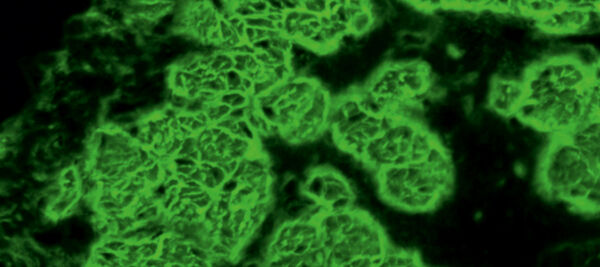

Nachweis zirkulierender IgA-Autoantikörper gegen Endomysium mittels indirekter Immunfluoreszenz auf Ösophagus